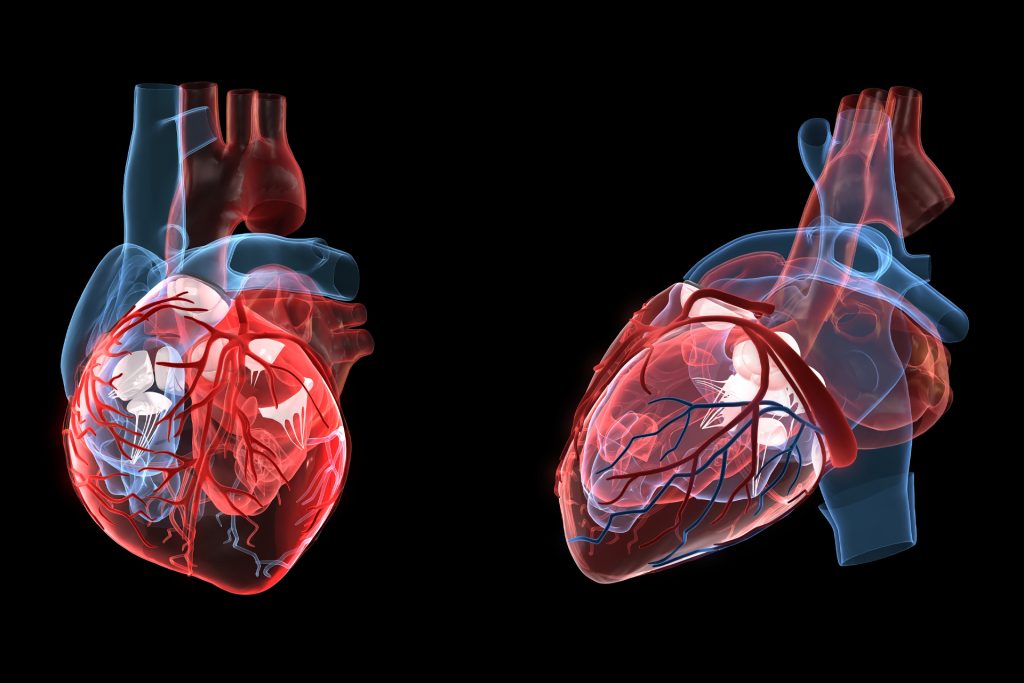

الرجفان الأذيني

يُعتبر الرجفان الأذيني اضطرابا في نظم القلب يؤدي إلى تسارع ضربات القلب بشكل غير منتظم، مما قد يتسبب في تكوّن جلطات دموية في القلب، وبالتالي يزيد من خطر الإصابة بالسكتة الدماغية.